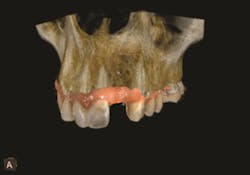

The interactive implant planning software provides multiple views, enabling the clinician to evaluate potential implant receptor sites with greater accuracy. Through the software, bone can be “removed” or displayed with transparency, which helps in determining the precise placement of implants, abutments and translucent virtual teeth in proximity to the natural tooth root structure. A virtual crown is used to guide the placement of the virtual implant for optimal aesthetics and function. This allows for well-informed conclusions to be drawn about crown-to-implant ratio; implant diameter and length; and the design of the restoration in terms of screw or cement retention.3 Figures 4-5.

Figure 4

Figure 5